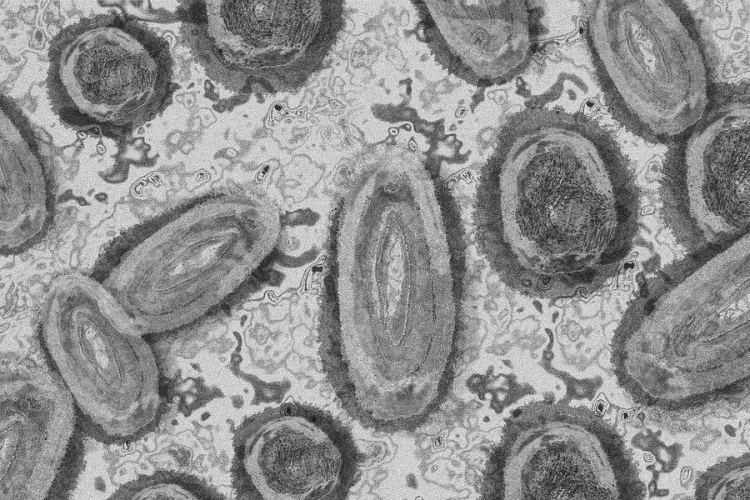

Meghaladta a 13 ezret a majomhimlő-fertőzöttek száma az Egyesült Államokban

Meghaladta a 13 ezret a majomhimlő-fertőzöttek száma az Egyesült Államokban, a legtöbb esetet Kaliforniában és New York államban regisztrálták.

Tovább nőtt a majomhimlő-fertőzöttek száma Magyarországon

Újabb kilenc, 23-50 éves férfinél igazolták a majomhimlő-fertőzést Magyarországon, ezzel 42-re nőtt a fertőzöttek száma - közölte a Nemzeti Népegészségügyi Központ (NNK) csütörtökön az MTI-vel.

Tovább nőtt a majomhimlő magyar fertőzöttjeinek száma

Újabb hat embernél diagnosztizálták a majomhimlő vírusát, így harmincra emelkedett az igazolt fertőzöttek száma Magyarországon - közölte a Nemzeti Népegészségügyi Központ (NNK) pénteken az MTI-vel.

Újabb hét magyarnál igazolták a majomhimlőt

Újabb hét embernél igazolták a majomhimlőfertőzést a Nemzeti Népegészségügyi Központ (NNK) veszélyes kórokozókkal foglalkozó laboratóriumában; ezzel 19-re nőtt az igazolt majomhimlő fertőzöttek száma Magyarországon